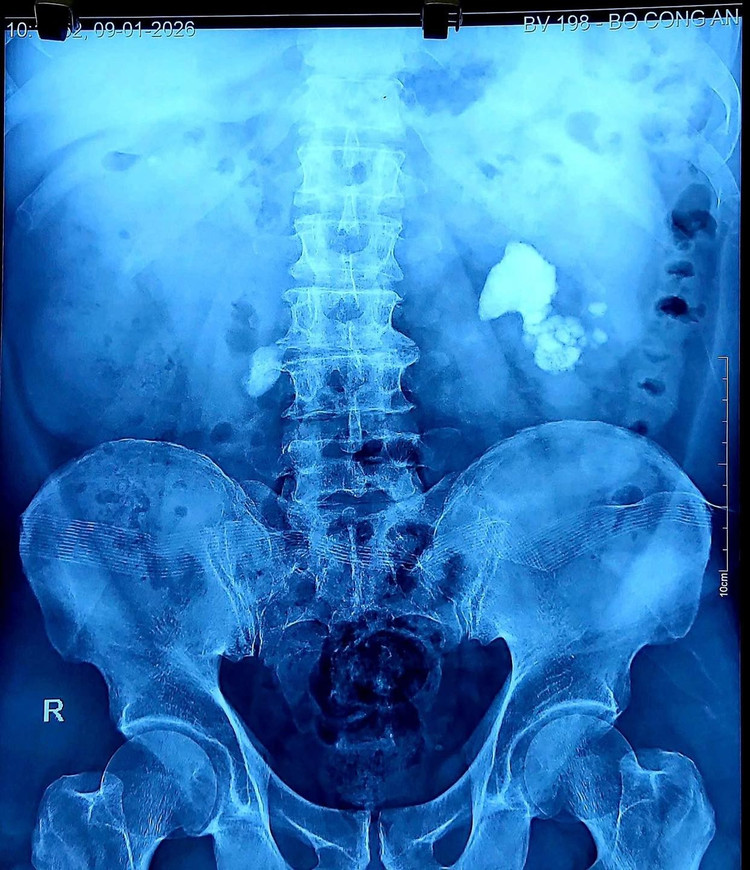

Thận ứ nước vì sỏi trên phim chụp - Ảnh BVCC

Kết quả thăm khám cho thấy: Ứ nước thận trái độ IV; Ứ nước thận phải độ III; Suy thận cấp do sỏi hai thận gây tắc nghẽn.

Trên phim CT: Thận trái giãn mỏng, gần như mất hoàn toàn chức năng; Thận phải còn hoạt động, nhưng đã suy giảm nặng.